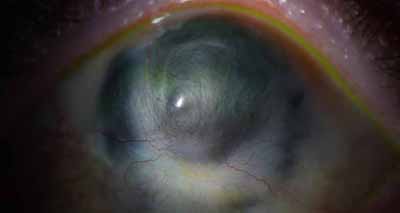

Aspecto Clínico

• Superficie corneal irregular y grisacea

• Opacidades granulares en parche

• Formación de lineas epiteliales elevadas de aspecto granular, que pueden dar imágen de seudodendritas

• Opacidades superficiales satélites

• Ulceración epitelial variante

• Formación de anillo inmunológico

• Dolor intenso (no siempre presente)

Superficie corneal irregular y grisácea